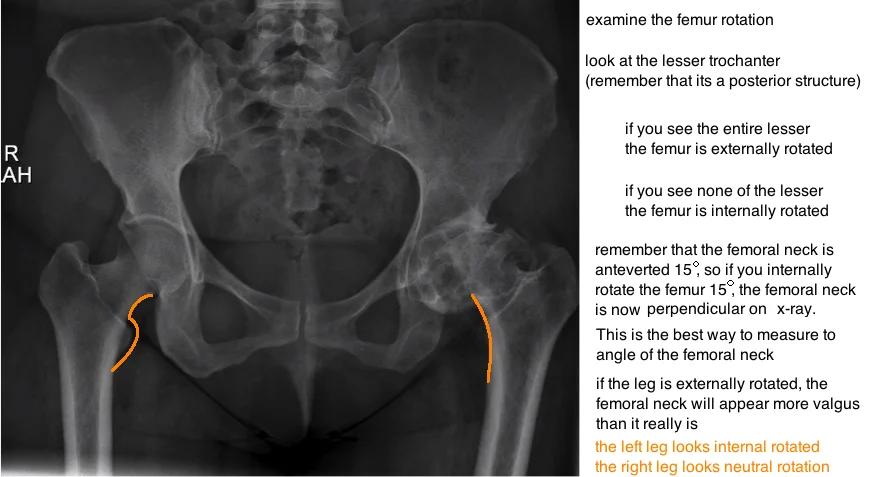

evaluating hip rotation on xray ap pelvis

femoral rotation on pelvis xray

measure femoral neck angle on ap pelvis